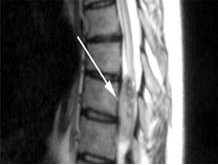

椎管內(nèi)腫瘤 椎管內(nèi)腫瘤術(shù)中